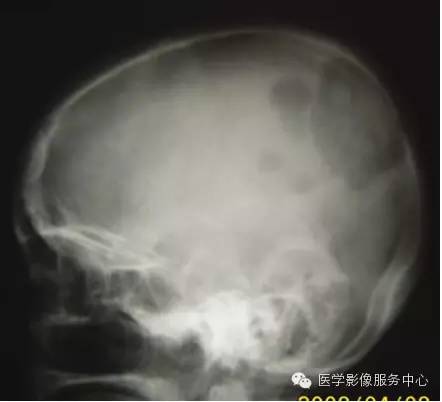

甲状腺癌骨转移

甲状腺癌的骨转移仅次于前列腺癌和乳腺癌,约占50%。由于甲状腺癌恶性程度差别很大,所以甲状腺癌骨转移的临床及X线片表现较特殊。临床表现常不明显,往往以转移瘤为首发表现:无痛性肿块,多为鸡蛋大小,质软,无压痛,边缘清楚,皮肤颜色正常,听诊有血管杂音,可抽出暗红色血性液体。

X线片表现:甲状腺癌骨转移,好发于颅骨、肋骨、脊柱、骨盆及肱骨、股骨近端;溶骨性破坏为主,呈大片状或地图样骨缺损。有时是多囊状破坏区,病变内有骨性间隔,此征象被认为是甲状腺癌骨转移的特征性表现。颅骨的破坏以外板为主,残留骨嵴大多与颅骨垂直。少数病例有骨膜反应。